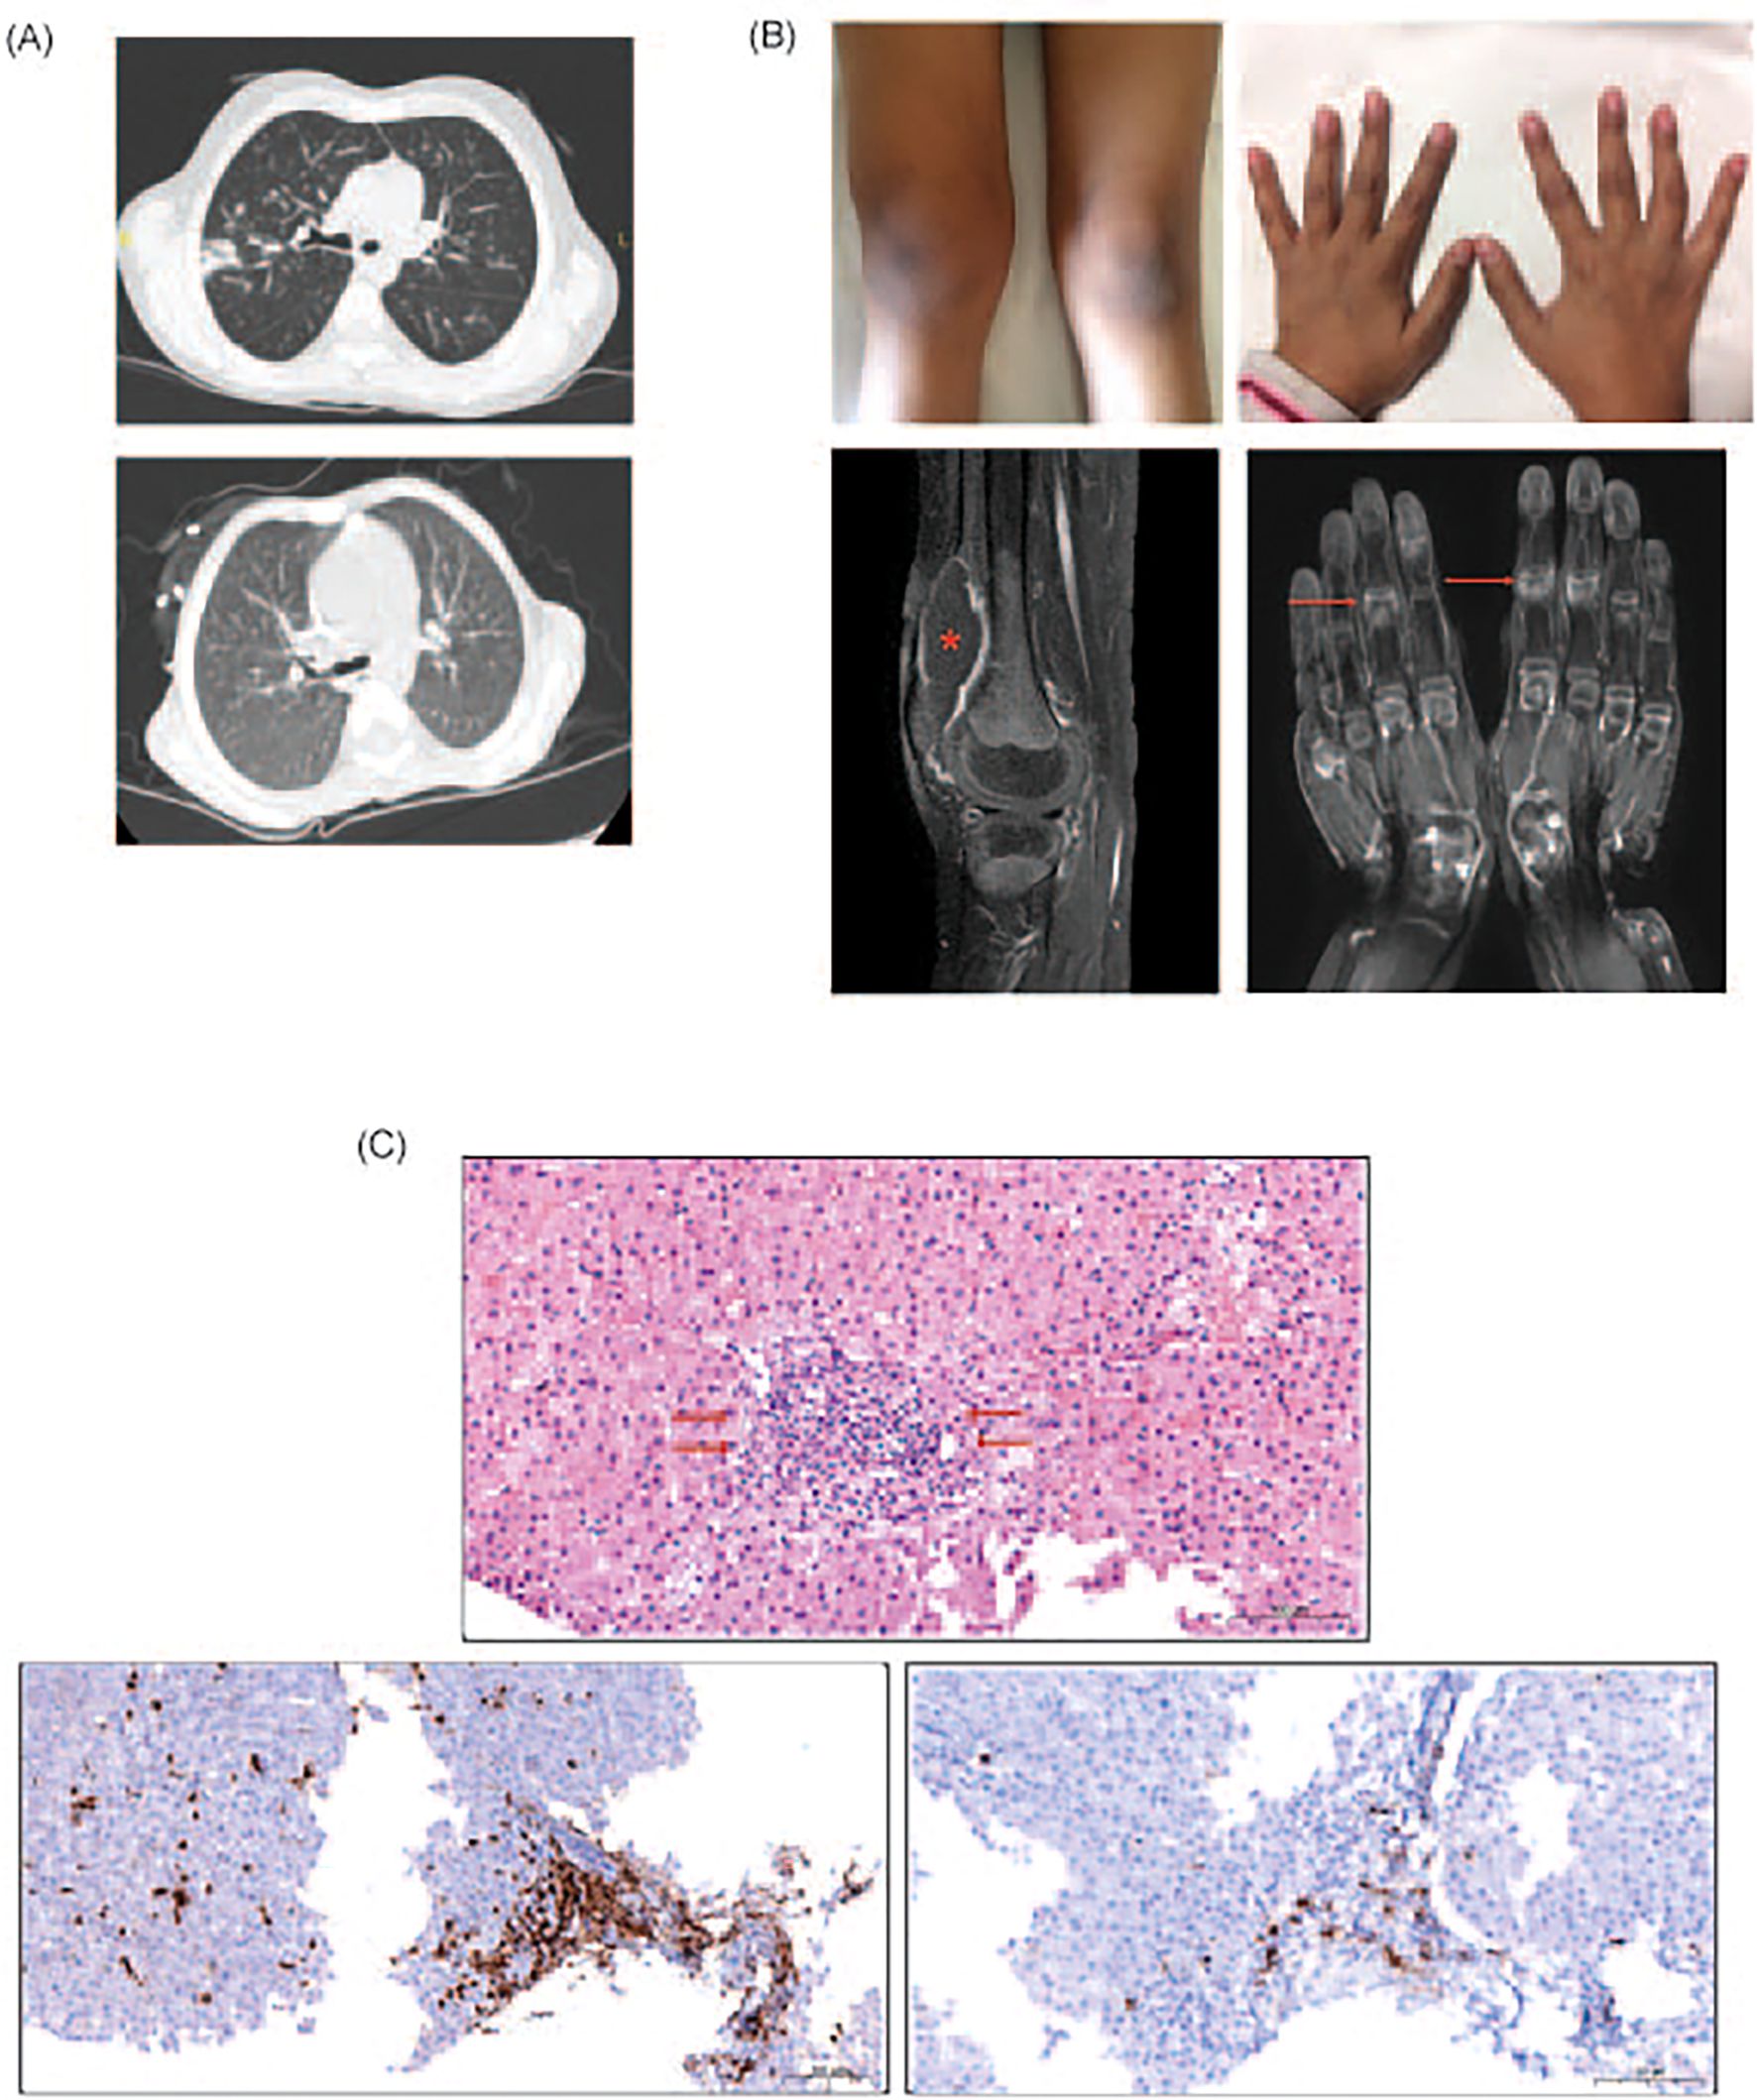

Patient 1 (P1) was a 9-year-old girl born to consanguineous parents, with a family history of a younger brother who died at the age of 2 years from suspected combined immunodeficiency. She was diagnosed with combined immunodeficiency based on clinical diagnosis and underwent allogeneic HSCT from a 10/10 matched unrelated donor following a reduced-toxicity conditioning regimen. Early post-transplant complications included mild skin graft-versus-host disease (GvHD), managed with cyclosporine, and cytomegalovirus (CMV) antigenemia, which responded to ganciclovir. Full donor chimerism was achieved, and immunosuppression and IVIG were discontinued after 10 months. However, at 24 months, she developed persistent CMV viremia and hypogammaglobulinemia, requiring irregular IVIG replacement. Bronchiectasis and pneumonitis (Figure 1A) due to Pseudomonas aeruginosa and CMV were later diagnosed, with CMV detected in bronchoalveolar lavage and resistant to ganciclovir but responsive to foscarnet. At 42 months, she developed seropositive inflammatory arthritis involving multiple joints (Figure 1B), resistant to non-steroidal anti-inflammatory drugs (NSAIDs) and steroids, but partially controlled with methotrexate. 2 doses of rituximab were administered and anti-BAFF treatment was planned, but she ultimately succumbed to Aspergillus pneumonia and myocarditis with malignant arrhythmia, despite extracorporeal membrane oxygenation (ECMO) support.

Figure 1

(A) Upper panel: Axial computer tomography (CT) image showing thickened bronchial walls and pneumonic infiltration in right upper lobe posterior segment. Image is from the episode where Aspergillus fumigatus was isolated from the bronchoalveolar lavage fluid of P1. Lower panel: Follow-up CT image demonstrating the complete resolution of the pneumonia. (B) Upper panel: Photos of arthritis on right knee and interphalangeal joints of P1 Lower panel: Contrast-enhanced MRI mages of both hands in coronal plan and right knee in sagittal plan showing synovial enhancements and inflammatory changes in interphalangeal and intercarpal joints (indicated with arrows). Please note the large effusion in the right knee (asterisk). (C) Upper panel: Hematoxylin eosin staining of the liver specimen from P3 showing the lymphocytic infiltration (indicated with arrow) at the periportal area in liver. Lower panel left: Immunohistochemistry staining of the liver specimen showing the CD3 positive lymphociytic infiltration at the periportal area Lower panel right: Immunohistochemistry staining of the liver specimen showing CD20 positive lymphocytic infiltration.

Autoimmune manifestations were not observed in the initial two years post-HSCT, mirroring the latency commonly reported for immune reconstitution-related complications. However, in the fourth post-transplant year, patient P1 developed seropositive oligoarticular arthritis (Figure 1B), accompanied by detectable anti-SSA and anti-SSM autoantibodies, despite persistent hypogammaglobulinemia and a paucity of class-switched memory B cells. The inflammatory arthritis was recalcitrant to conventional immunomodulators including methotrexate and rituximab. Initiation of anti-BAFF therapy was under consideration when the patient succumbed to septicemia. Patient P3 manifested signs of immune dysregulation at 24 months post-HSCT, initially presenting with ashy dermatosis followed by biochemical and serological evidence of hepatitis with anti-LKM1 autoantibodies. Histopathological evaluation of liver tissue could not definitively distinguish autoimmune hepatitis from GvHD. The hepatic involvement was refractory to multiple immunosuppressive regimens, including systemic corticosteroids, mesenchymal stromal cell infusions, mycophenolate mofetil, rapamycin, and tacrolimus. Retrospective re-evaluation of liver biopsy showed T and B cell infiltration in the periportal area (Figure 1C), similar to the pathology observed in patients with LTβR deficiency (18) and murine models of NIK deficiency (19). Collectively, the autoimmune pathology observed in these individuals phenocopies the autoimmunity seen in murine models deficient in NIK or LTβR signaling (8, 9, 13, 15, 24), further supporting the indispensable role of NIK within mTECs for the establishment of central tolerance in humans (28).